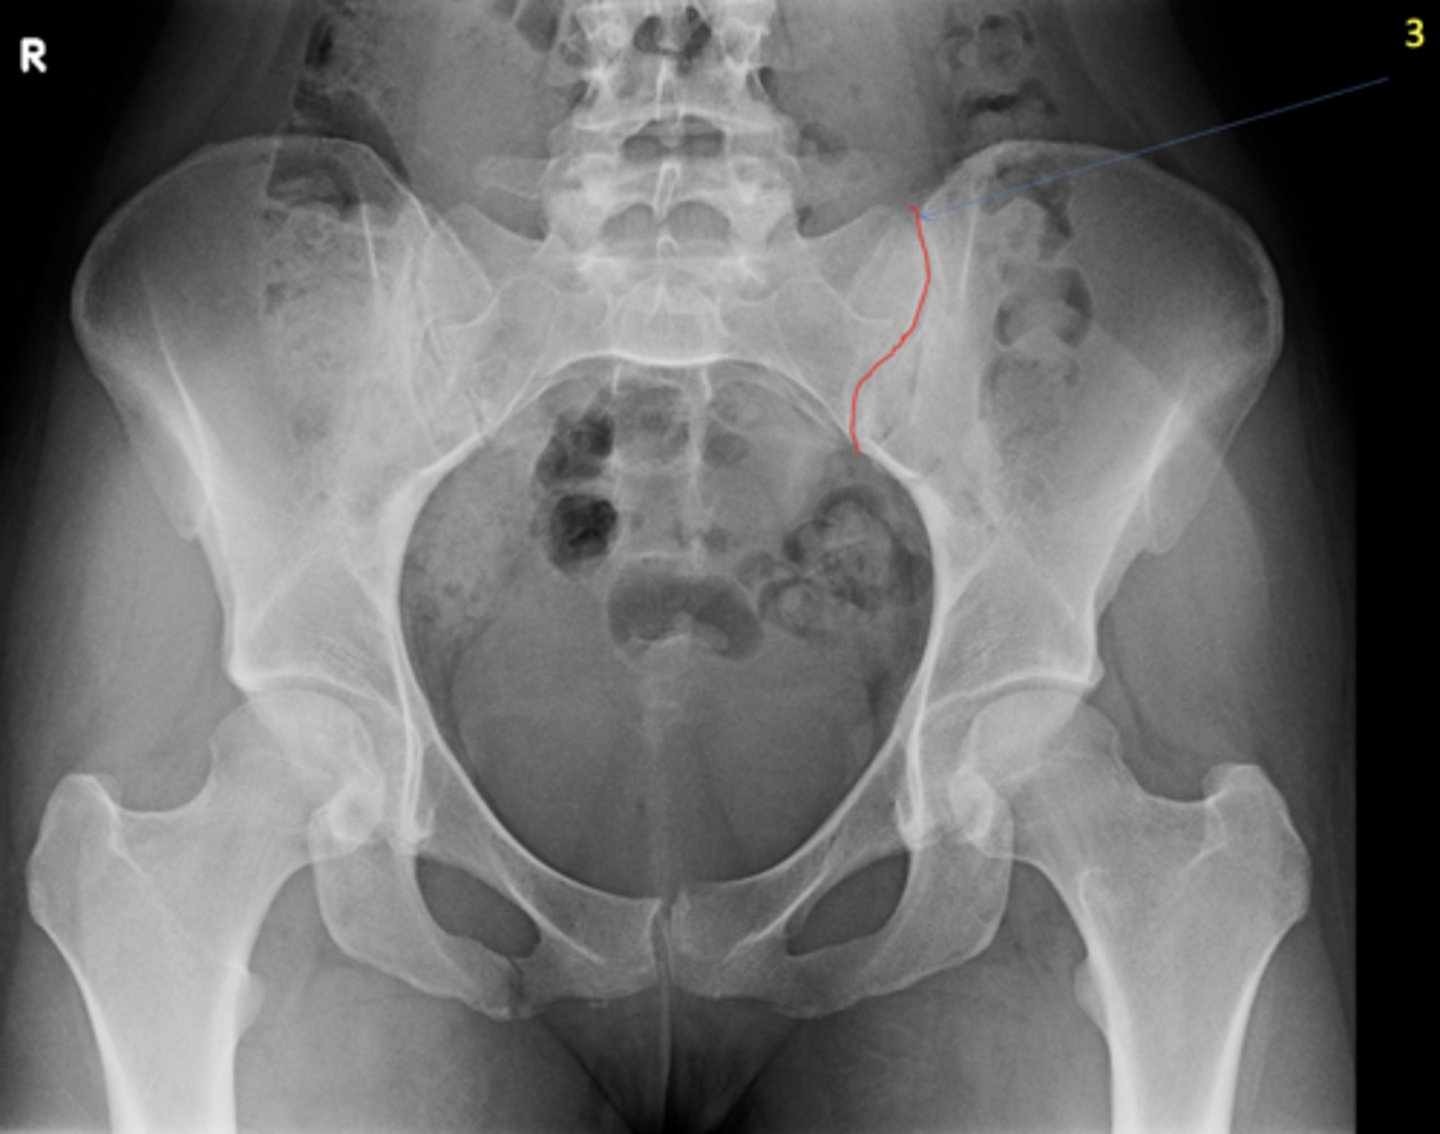

Left posterior sacroiliac joint

ID 3 (joint)

<p>ID 3 (joint)</p>

Left anterior sacroiliac joint

ID 4 (joint)

<p>ID 4 (joint)</p>

Left femoroacetabular joint

ID 2 (joint)

<p>ID 2 (joint)</p>